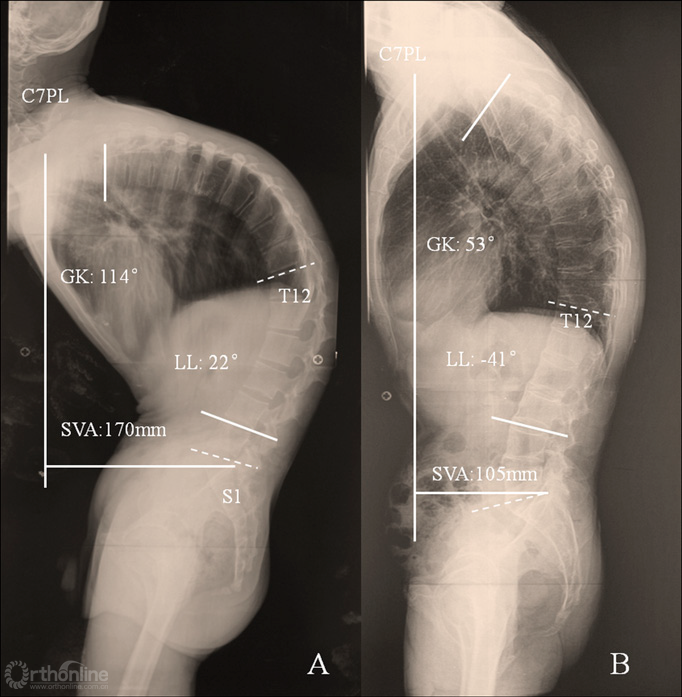

图10 骶骨倾斜角负值患者与骶骨倾斜角正值患者的矢状位对比

(图片资料摘自Qian等The Presence of a Negative Sacral Slope in Patients with Ankylosing Spondylitis with Severe Thoracolumbar Kyphosis, J Bone Joint Surg Am, 2014, 96(22):e188.)